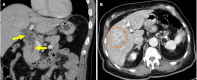

Endoscopic retrograde cholangiopancreatography (ERCP) is a cornerstone procedure for the diagnosis and management of pancreatic and hepatobiliary diseases. Although its diagnostic role has been increasingly supplanted by noninvasive imaging modalities such as magnetic resonance imaging (MRI) and magnetic resonance cholangiopancreatography, the therapeutic applications of ERCP have continued to expand. ERCP is widely used and has a generally favorable safety profile. However, it is important to recognize expected post-procedural imaging findings and serious complications that can arise. The increasing complexity of therapeutic interventions and the growing volume of procedures have led to a higher incidence of complications that often present with overlapping clinical and laboratory features, underscoring the critical role of imaging in differential diagnosis. This review focused on the typical normal ERCP findings and the imaging characteristics of common complications, including pancreatitis, bleeding, ERCP-related infections, perforations, and stent-related complications. Computed tomography (CT) is particularly valuable in timely recognition, management, and surgical decision-making for these complications. Furthermore, MRI offers a radiation-free alternative for managing complications in selected patients. Therefore, radiological modalities, particularly CT and MRI, are critical tools for the rapid diagnosis, management, and surgical decision-making processes for post-ERCP complications.